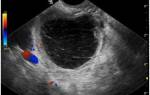

Специалисты отмечают, что перед операцией необходимо провести тщательную диагностику, включая УЗИ и анализы, чтобы точно определить локализацию беременности. Важно также учитывать общее состояние здоровья женщины и наличие сопутствующих заболеваний. После операции пациентки обычно нуждаются в наблюдении и поддерживающей терапии, чтобы восстановить репродуктивное здоровье. Таким образом, сальпингоофорэктомия требует комплексного подхода и индивидуального плана лечения для каждой пациентки.

На этом этапе пациентка проходит ряд исследований. Это УЗИ, анализы крови. При необходимости – ЭКГ и другие исследования, которые помогут установить, нормально ли пациентка перенесет наркоз. За сутки до манипуляции однократно вводится дневная доза антибиотика. Делается это для снижения вероятности воспалительных процессов.

Лапароскопия при внематочной беременности проводится под наркозом. Через небольшие проколы в живот вводят оптическую систему, которая позволяет врачу увидеть характерное утолщение фаллопиевой трубы с усиленным сосудистым рисунком, наличие крови в брюшной полости.